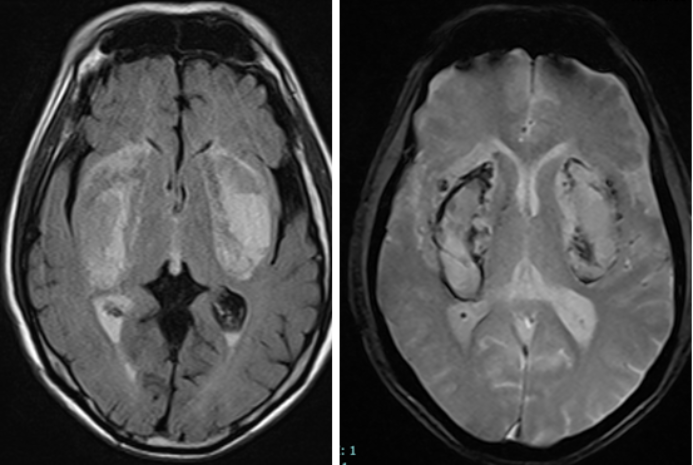

Trường hợp thứ 2, nam bệnh nhân 66 tuổi sau khi uống phải cồn pha nước lọc 1 ngày xuất hiện tình trạng đau đầu, nhìn mờ dần, vật vã kích thích. Bệnh nhân nhập viện trong tình trạng hôn mê sâu, toan chuyển hóa nặng do ngộ độc methanol. Kết quả chụp cộng hưởng từ sọ não cho thấy tổn thương nhồi máu, hoại tử, chảy máu nhân bèo hai bên - đây là dạng tổn thương não điển hình do ngộ độc methanol. Người bệnh dù được hồi sức tích cực, lọc máu, thở máy nhưng tình trạng rất nặng, nguy cơ cao đối mặt với tình trạng sống thực vật.